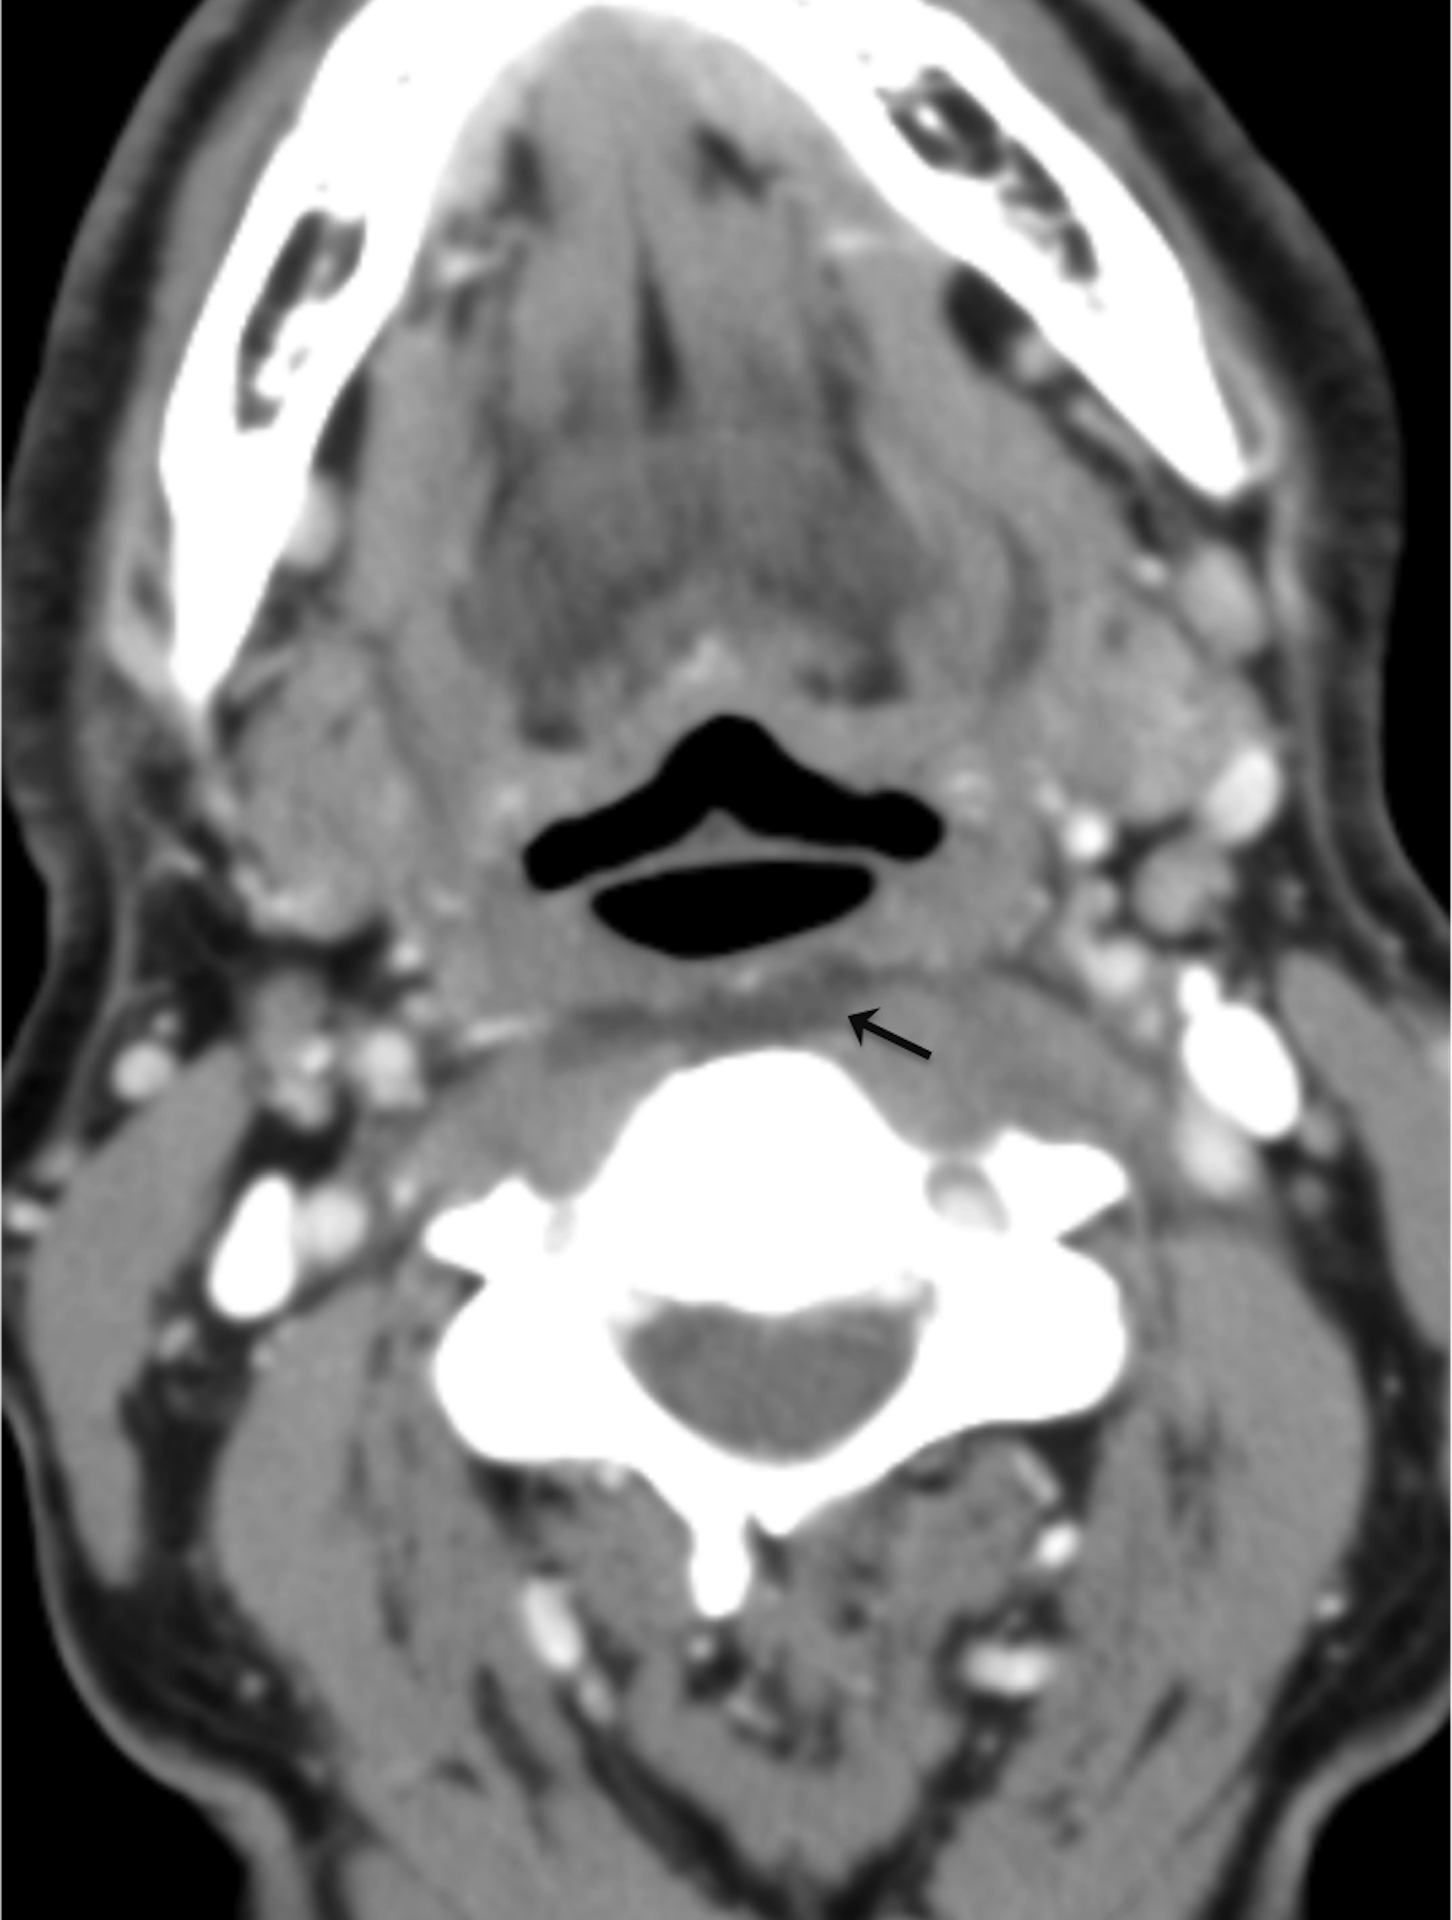

Acute calcific tendinitis of the longus colli (CTCL) is a rare, self-limited and probably under diagnosed cause of acute neck pain in which the radiologist can make a definitive diagnosis. It commonly mimics potentially serious conditions affecting the retropharyngeal space. We report a case of a 63-year old male presenting in the emergency department with acute throat pain. Imaging findings were diagnostic of CTCL. A brief review of the literature is provided.